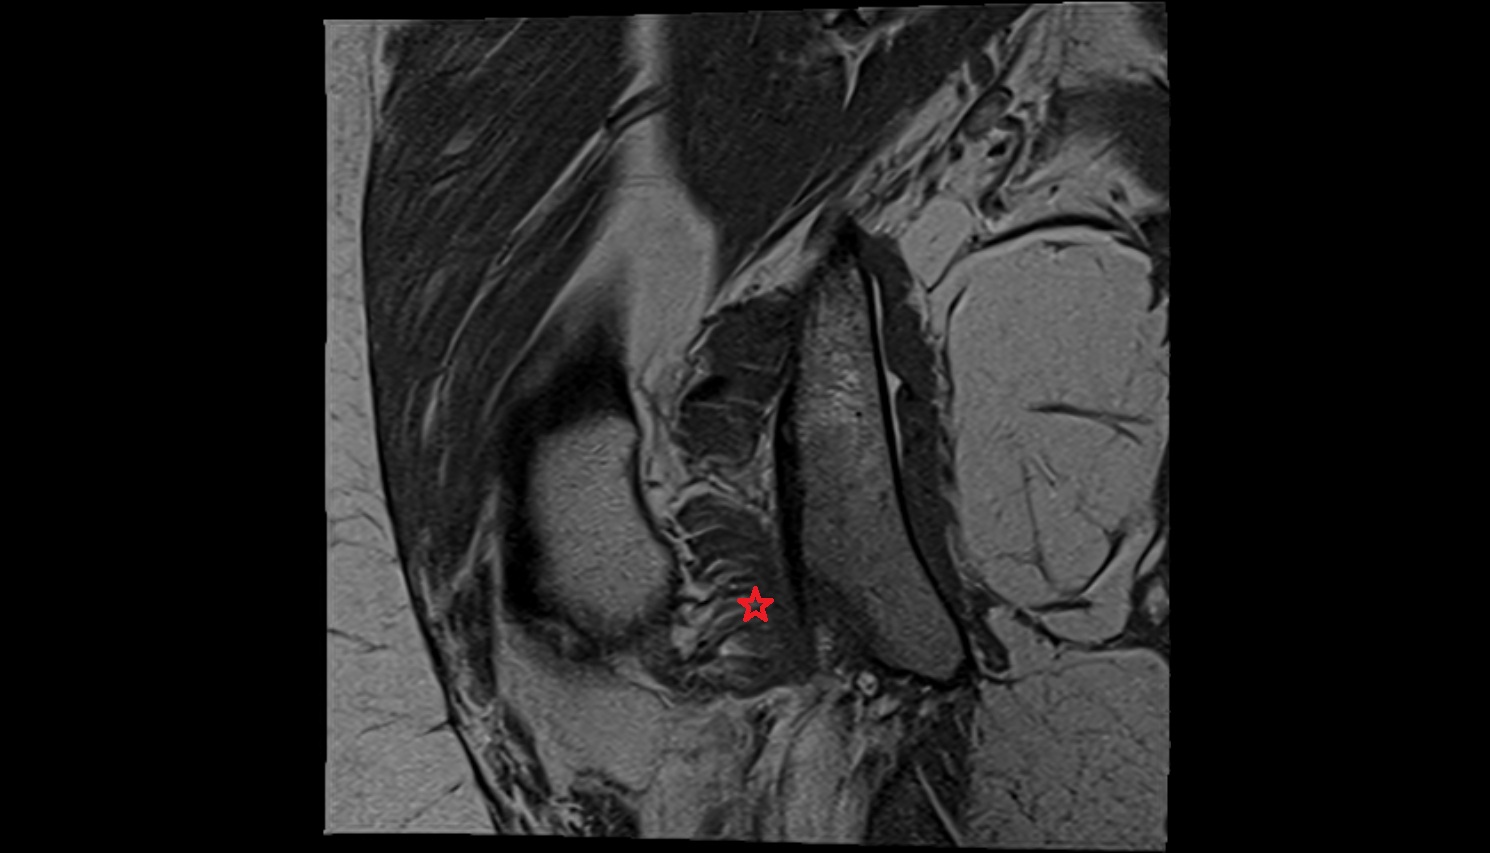

- Anterior cruciate ligament